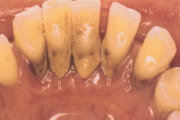

Krooniline parodontiit

Krooniline parodontiit on mikroobide poolt põhjustatud hammaste tugikudede põletik, mille tulemusena tekib progresseeruv alveolaarluu (nähtav röntgenograamil) ja periodontaalligamendi destruktsioon, igemetaskute moodustumine, igeme retsessioon või mõlemad kahjustused kombineeritult. Loe edasi »

- igemepiir on taandunud (3)

- luu destruktsioon (5)

- hamba kinnitussidemete kadu (3)

- puudulik suuhügieen (5)

- igemepealne hambakivi (5)

- igemealune hambakivi (4)